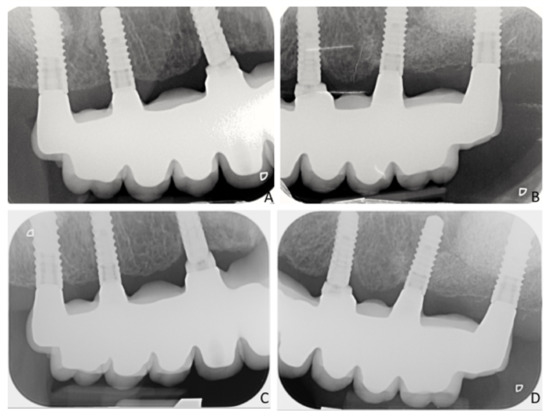

| MBL Short | MBL Control | Progressive Changes Short | Progressive Changes Control | |

|---|---|---|---|---|

| Prosthesis delivering (BL) | 0.17 ± 0.41 | 0.28 ± 0.21 | NA | NA |

| 6 months | 0.18 ± 0.34 | 0.49 ± 0.44 | −0.01 ± 0.11 | −0.21 ± 0.33 |

| 12 months | 0.21 ± 0.35 | 0.58 ± 0.44 | −0.04 ± 0.13 | −0.30 ± 0.32 |

| 18 months | 0.34 ± 0.35 | 0.68 ± 0.51 | −0.17 ± 0.29 | −0.40 ± 0.37 |

| 24 months | 0.44 ± 0.37 | 0.84 ± 0.68 | −0.28 ± 0.37 | −0.54 ± 0.49 |